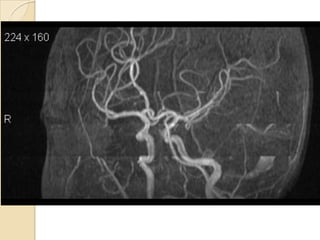

Arteries of the brain (lateral view) - MRA

1. Anterior cerebral artery

2. Anterior communicating artery

3. Basilar artery

4. branches (in insula) of middle cerebral artery

5. Cavernous portion of internal carotid artery

6. Cervical portion of internal carotid artery

7. Genu of middle cerebral artery

8. Intracranial (supraclinoid) internal carotid artery

9. Middle cerebral artery

10. Ophthalmic artery

11. Petrous portion of internal carotid artery

12. Posterior cerebral artery

13. Posterior cerebral artery in ambient cistern

14. posterior cerebral artery in interpeduncular

cistern

15. Posterior communicating artery

16. Posterior inf cerebellar artery.

17. Quadrigeminal portion of posterior cerebral

artery

18. Superior cerebellar artery

19. Vertebral artery